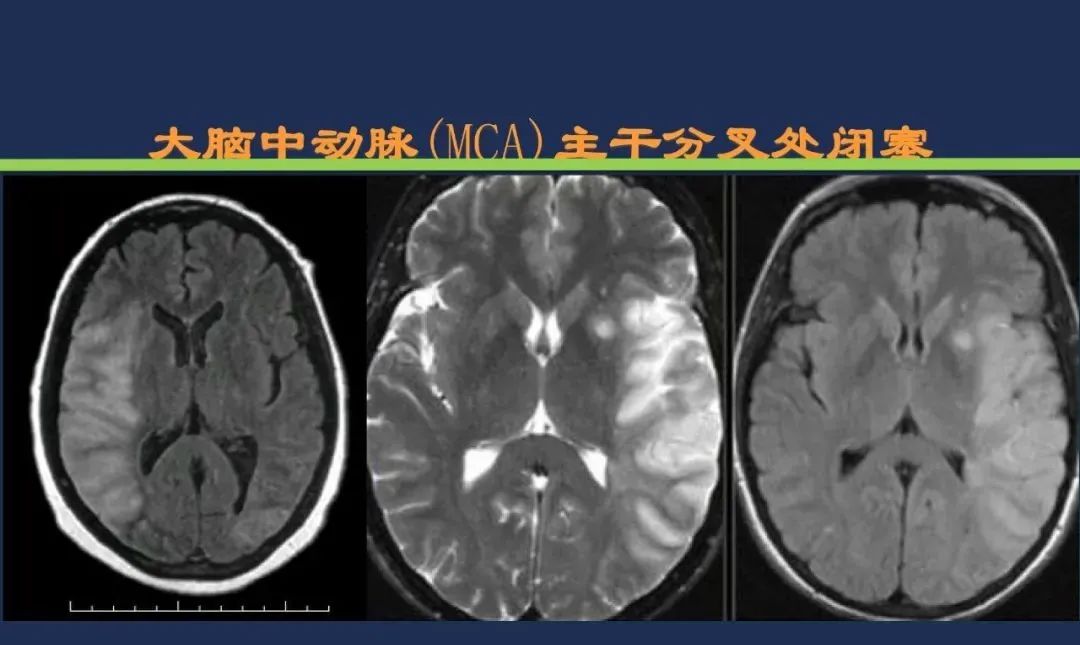

颈内动脉系统梗死颈内动脉大脑中动脉